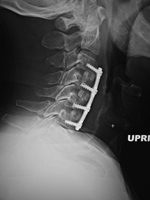

53 year-old man with disk herniation. Anterior cervical fusion plate spans C3 to C6. Interbody disk bone plugs (spacers) are present at C3-4, C4-5, and C5-6.

Anterior cervical fusion plate - AP view Anterior cervical fusion plate - lateral view Cervical spine fusion cage and anterior cervical fixation plate Cervical spine interverterbral disk fusion cage

Zero-P (DePuy Synthes) low Profile anterior interbody fusion device Zero-P (DePuy Synthes) low Profile anterior interbody fusion device